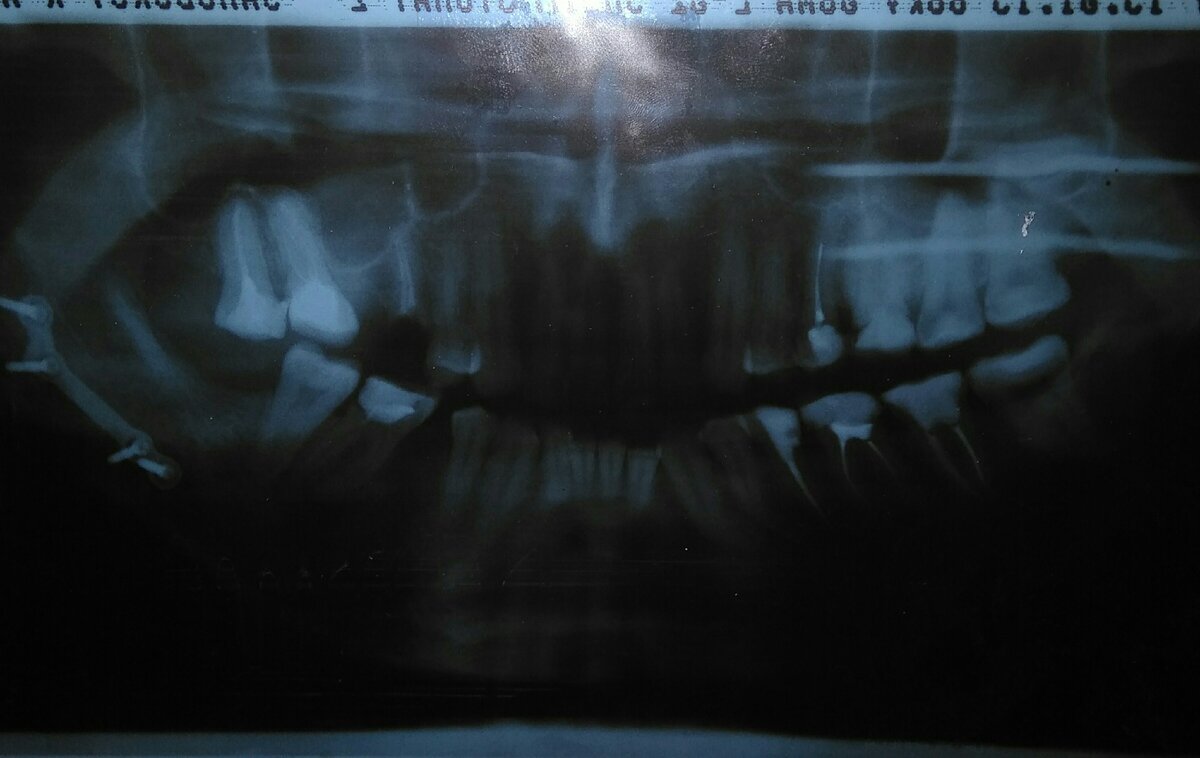

Сломанная челюсть. Часть #3.

Сначала, вообще, подумал, что только зуб сломал. Сказал Ване, что пойду к себе в комнату. Потом сообразил... Я всегда считал, что раз уж заболел, то должен обратиться к врачу. Поэтому как только понял, что моя нижняя челюсть распалась на несколько нижних челюстей, направился к знакомой ( женщине администратору ) и попросил её вызвать скорую. Моя просьба звучала слегка шепеляво, но понятно. Хотя, к моему сожалению, и не была выполнена: не могла администратор дозвониться до скорой. А какой-либо другой помощи предложить не могла. Справедливо решив, что спасение утопающих - дело рук самих утопающих, вышел из корпуса и стал вызывать медиков по мобильному. Вызвал. При общении, правда, приходилось одной рукой фиксировать челюсть, но главное результат. Не так ли? До приезда машины сходил к себе, чтобы собрать мыльно-рыльные принадлежности и смену одежды для больницы. Наивно ( как вскоре выяснилось ) полагал, что меня сразу госпитализируют. Скорая привезла меня, конечно, в больницу, но сразу сд

Я всегда считал, что раз уж заболел, то должен обратиться к врачу. Поэтому как только понял, что моя нижняя челюсть распалась на несколько нижних челюстей, направился к знакомой ( женщине администратору ) и попросил её вызвать скорую.